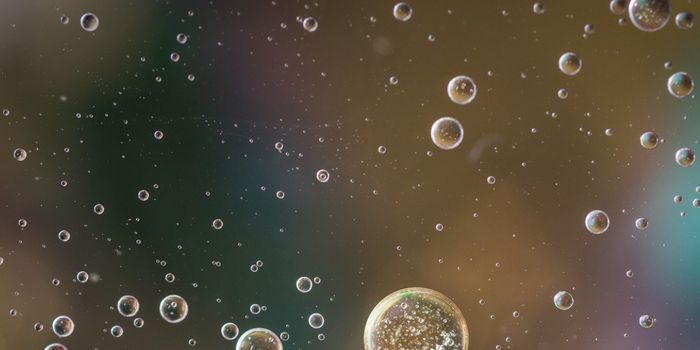

MAR 19, 2025Drug Discovery & DevelopmentFlowCam uses Flow Imaging Microscopy (FIM) to characterize particles in liquid biopharmaceutical formulations. There are ...

MAR 03, 2025Drug Discovery & DevelopmentFlow Imaging Microscopy for Particle Quantification and Characterization By: Austin Daniels, PhD, Application Scientist, ...